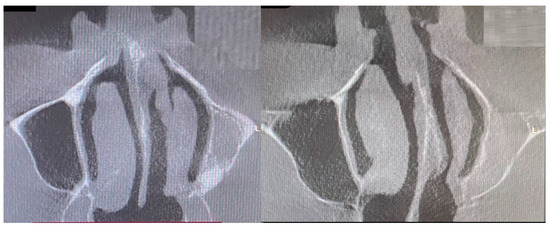

- Type 2 in-pure SSS (iSSS) (Figure 3, Figure 4 and Figure 6) related to maxillary deformation (might be related to maxilla-mandibular skeletal class II/III deformities or others), clinically asymptomatic, not related to trauma or surgery, 1–3 MS walls retracted, OMC clear, no opacification, like suggested by Lee et al., the “not so silent sinus” [18];